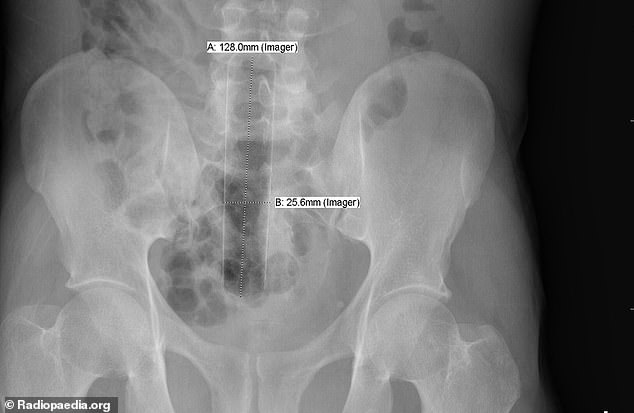

4. Μία μεταλλική θήκη πούρου